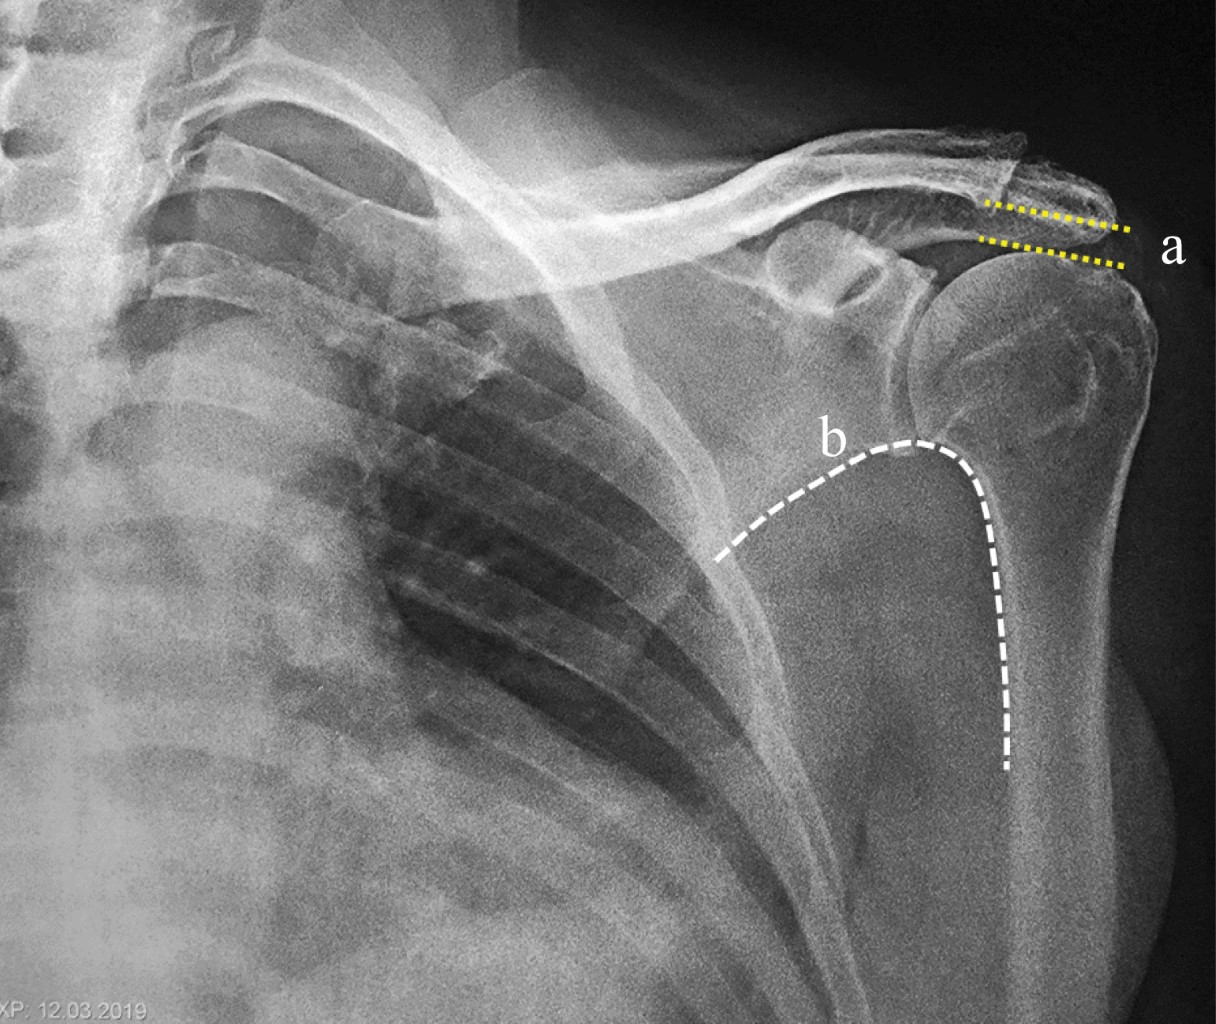

From www.medigraphic.com

Massive rotator cuff injury arthroscopic treatment with upper capsular reconstruction Rotator Cuff Capsular Pattern rotator cuff (rc) pathologies. Perhaps that's why the capsular patterns may be different. according to dutton, capsular patterns are based on clinical findings rather than research; The primary way to distinguish rc pathologies from frozen shoulder is to examine the specific. adhesive capsulitis (also known as frozen shoulder) is a condition of the shoulder characterized by functional. Rotator Cuff Capsular Pattern.

Massive rotator cuff injury arthroscopic treatment with upper capsular reconstruction Rotator Cuff Capsular Pattern rotator cuff (rc) pathologies. frozen shoulder can develop after a shoulder has been immobilized (held in one position without moving) for a period of time due to surgery, a fracture, or. according to dutton, capsular patterns are based on clinical findings rather than research; Perhaps that's why the capsular patterns may be different. examples include a. Rotator Cuff Capsular Pattern.

Massive rotator cuff injury arthroscopic treatment with upper capsular reconstruction Rotator Cuff Capsular Pattern rotator cuff (rc) pathologies. examples include a rotator cuff tear and fractures of your shoulder blade, collarbone or upper arm. The primary way to distinguish rc pathologies from frozen shoulder is to examine the specific. according to dutton, capsular patterns are based on clinical findings rather than research; adhesive capsulitis (also known as frozen shoulder) is. Rotator Cuff Capsular Pattern.

Massive rotator cuff injury arthroscopic treatment with upper capsular reconstruction Rotator Cuff Capsular Pattern stage 1, the preadhesive stage, demonstrates mild erythematous synovitis. The primary way to distinguish rc pathologies from frozen shoulder is to examine the specific. frozen shoulder can develop after a shoulder has been immobilized (held in one position without moving) for a period of time due to surgery, a fracture, or. examples include a rotator cuff tear. Rotator Cuff Capsular Pattern.